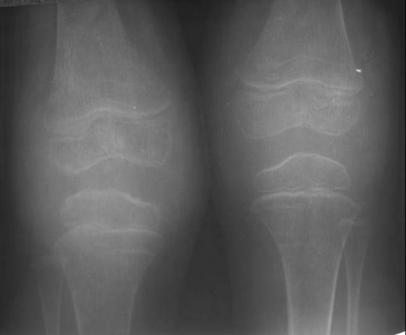

二、关节病型银屑病,

关节症状可出现在皮损之前、同时或之后,任何关节均可受累,包括肘膝的大关节,指、趾小关节、脊椎及骶髂关节,关节肿胀、疼痛,活动受限,严重时关节畸形,X线检查呈软骨消失、骨质疏松、关节腔狭窄伴不同程度的关节侵蚀和软组织肿胀,但RF阴性